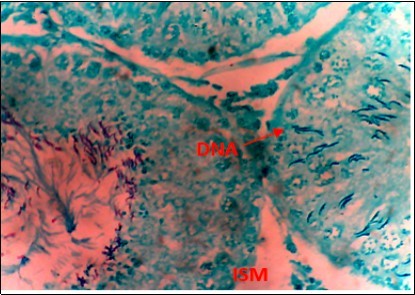

Figure 7.(DC+1000mg/kg.bw of AP) X400 – Section of testis showing scanty DNA deeply stained with magenta color. DNA strands has reduced clusters

(DC+1000mg/kg.bw of AP) X400 – Section of testis showing scanty DNA deeply stained with magenta color. DNA strands has reduced clusters

From findings in this study, irregular and distorted arrangements of DNA in all diabetic groups (Groups B, C, D, E and F) when compared with the normal control group, may have been due to displacement of sertoli cell within the germinal epithelium of seminiferous tubules. Strands of DNA were also seen arrange in clusters in diabetic groups, showing altered and defective structure which might have resulted from base free side deletion, frame shift, cross-linking and chromosomal rearrangement. The intensity of magenta colour development in Feulgen reaction for DNA demonstration was proportional to DNA concentration. There was reduced colour intensity in all diabetic groups (Groups B, C, D, E and F) when compared with the normal control. This is in line with report from Aitken and Krausz (2001). However the degree of distortion and cross-linking of DNA strand in the group of diabetic animal models placed on high dose (1000mg/kg.bw) of A. polytricha which may be a sign of amelioration. Groups C, D and F placed on 250mg/kg.bw A. polytricha, 500mg/kg.bw A. polytricha and standard anti-diabetic drug (metformin) respectively did not show remarkable differences in terms of DNA arrangements when compared with the diabetic control group. Groups D (500mg/kg.bw A. polytricha) and group E (1000mg/kg.bw) showed visible improvement in magenta colour intensity when compared with the diabetic control group.